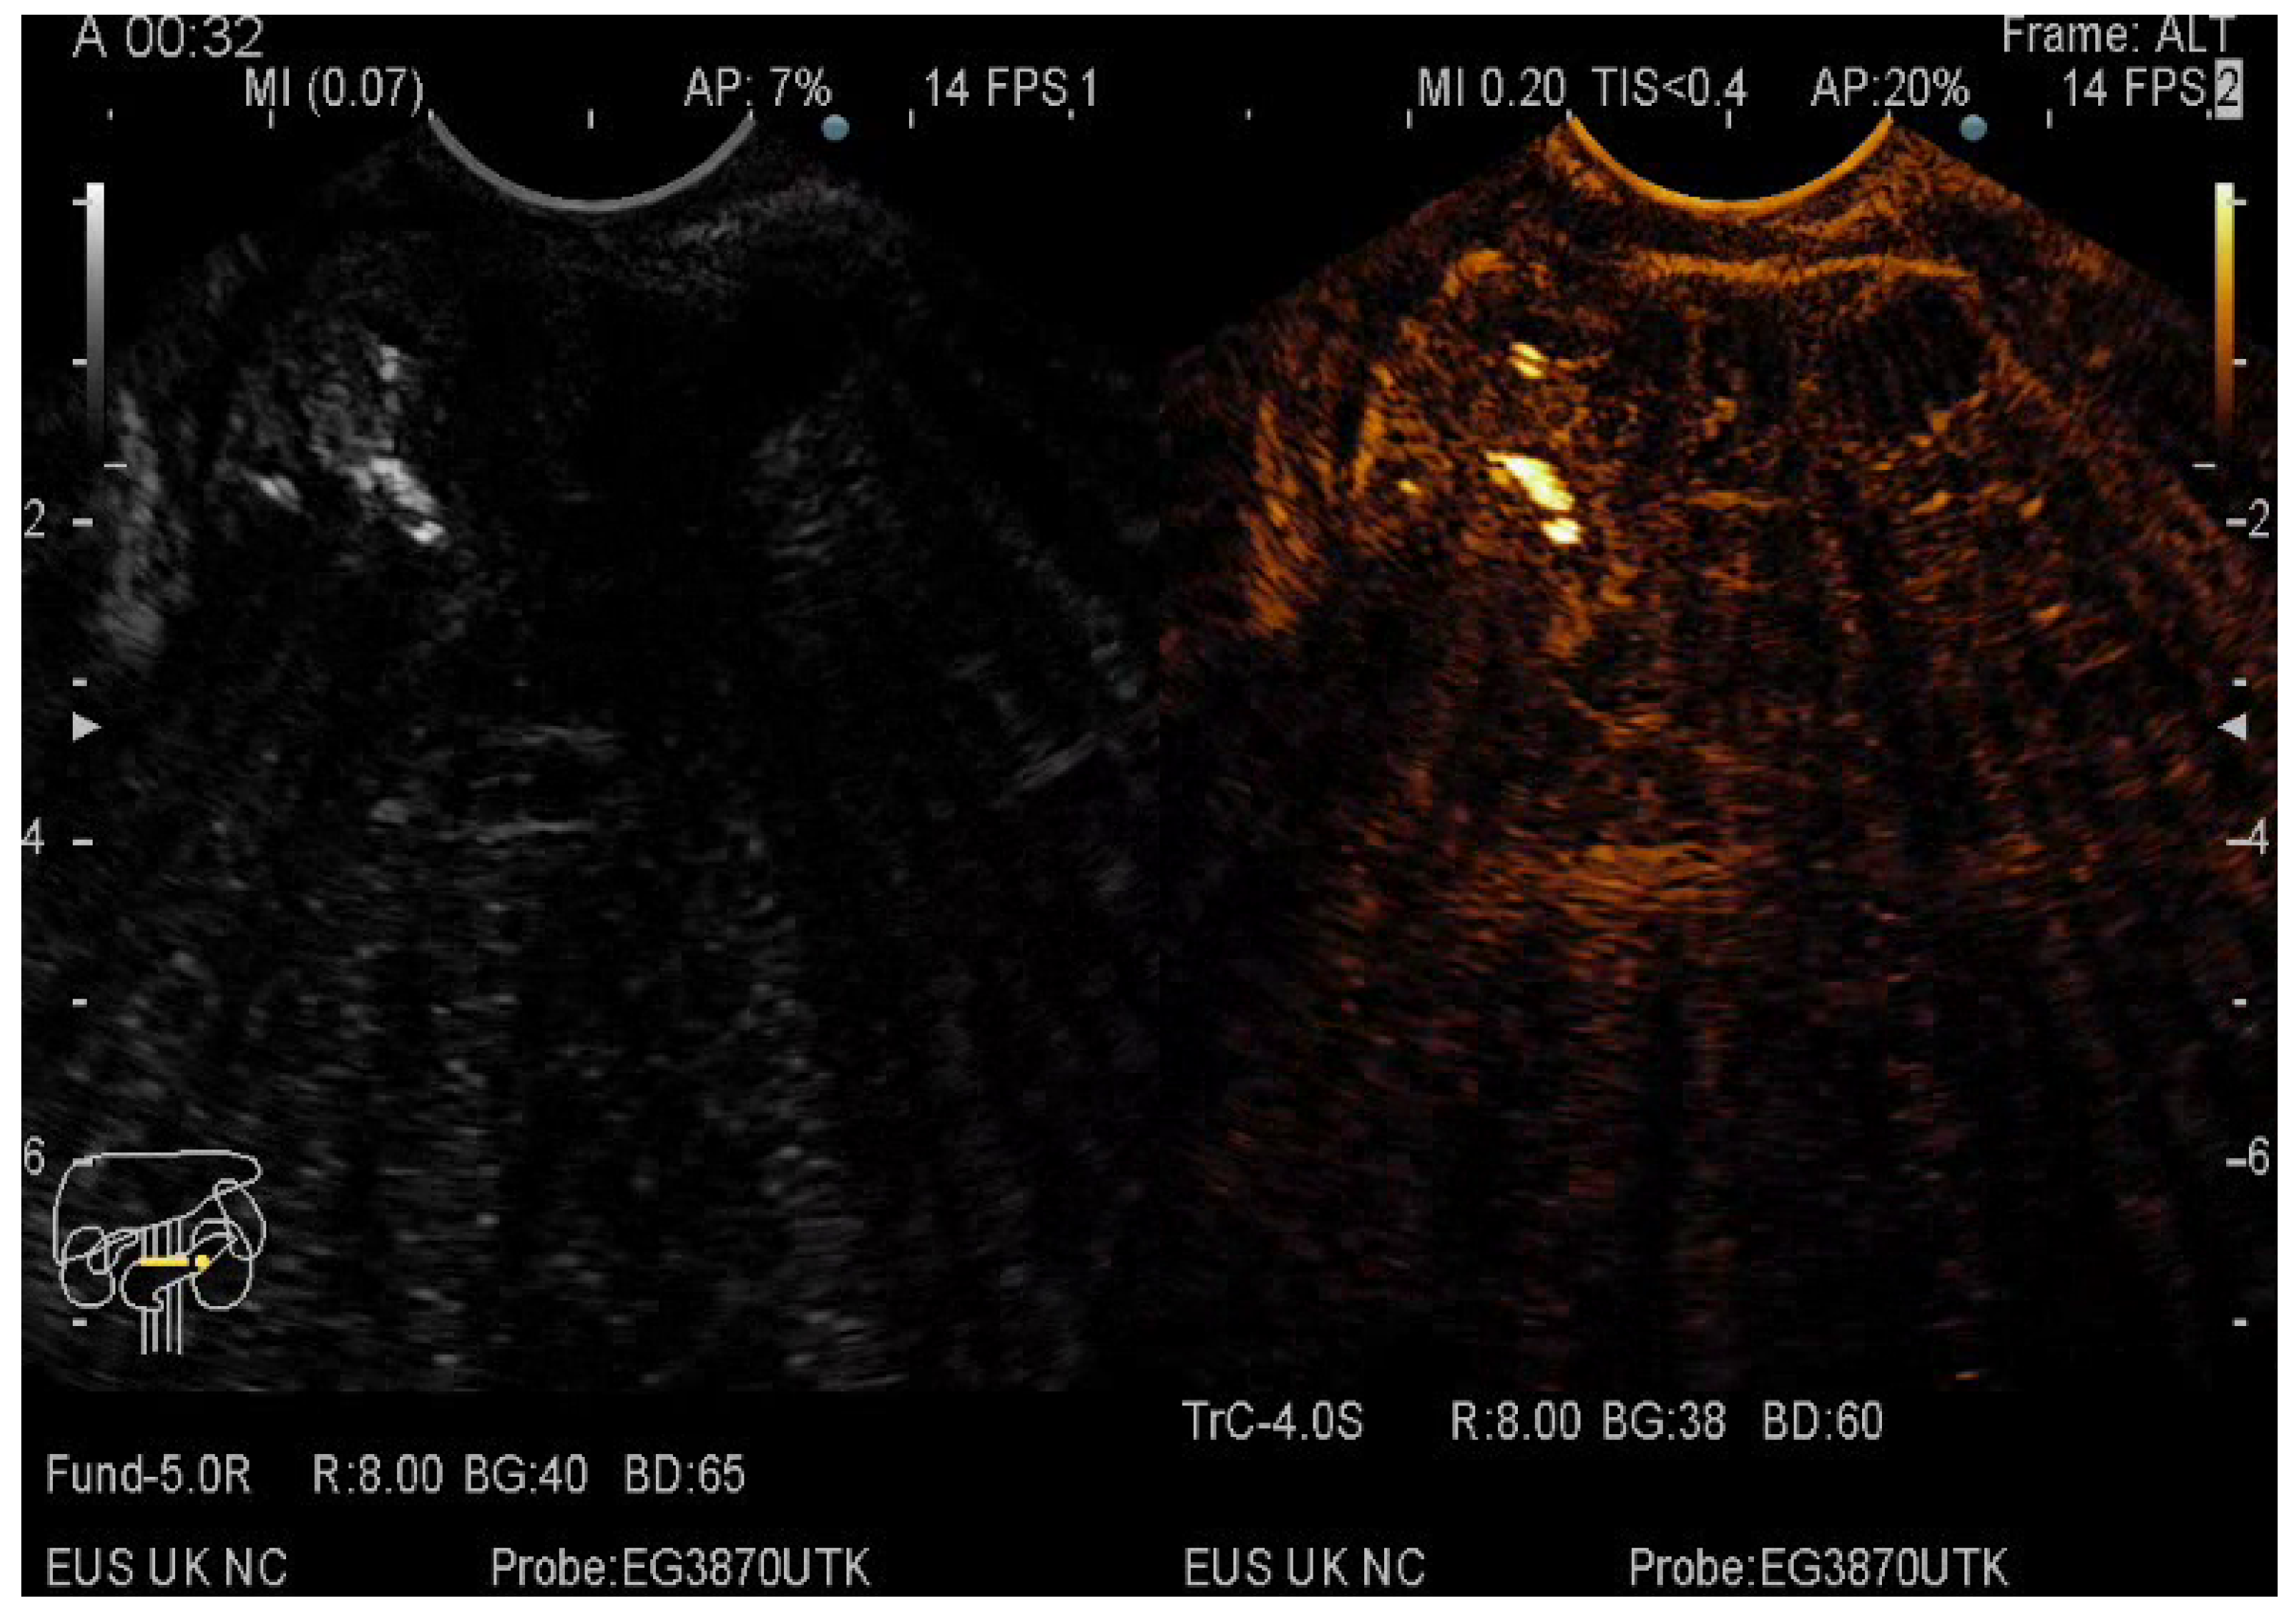

2.5. CE-EUS Procedure

3.3. EUS-FNA/FNB + CE-EUS of Pancreatic Cystic Lesions Subgroup